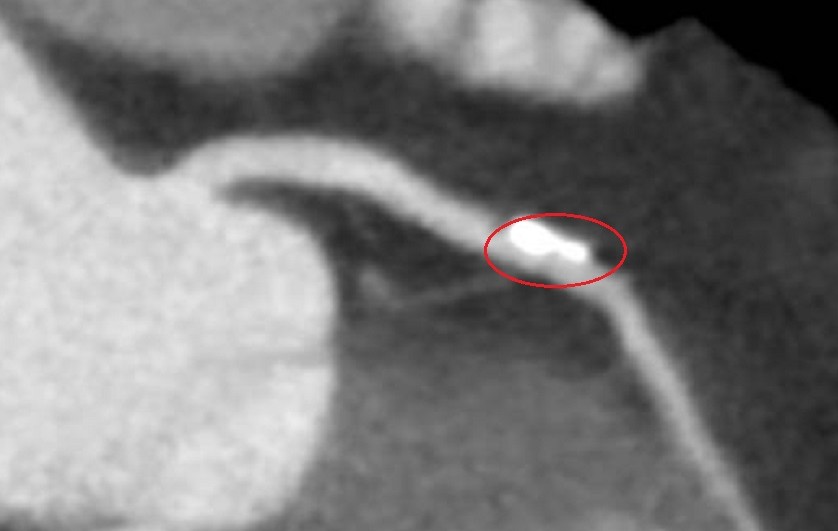

圖:電腦斷層顯示盧女鈣化斑塊(紅圈)。李學林醫師探視盧女。心導管手術植入生物適應性支架/彰化醫院提供

李學林醫師說,運動心電圖發現盧女士心血管缺血,電腦斷層發現左冠狀動脈的左前降支有一處約70%阻塞並鈣化,與病人共同決策,採IVL處理鈣化斑塊,再植入生物適應性支架,預期可達到最佳治療效果。